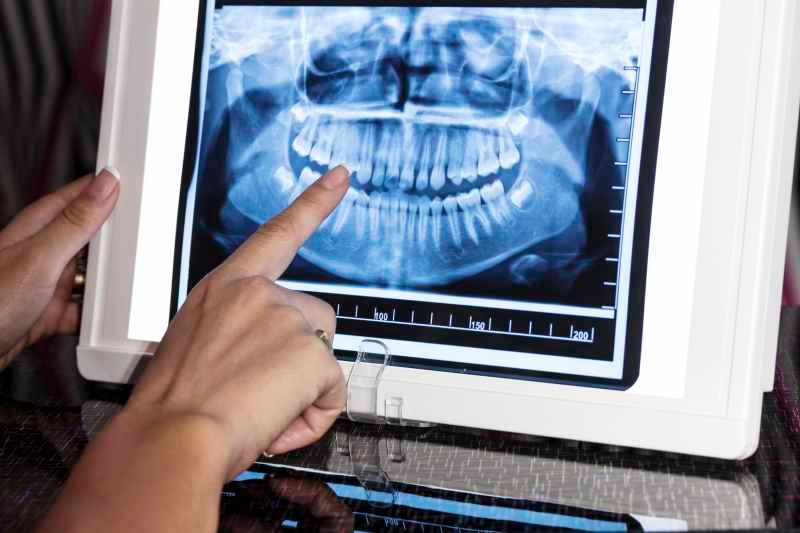

Cada diente está compuesto por varias capas, cada una con una función específica. La parte visible del diente, llamada corona, está cubierta por el esmalte, una capa dura y protectora. Bajo el esmalte se encuentra la dentina, una capa más blanda que constituye la mayor parte del diente. En el centro del diente está la pulpa dental, que contiene nervios y vasos sanguíneos.

La raíz del diente, que se encuentra debajo de la encía, está anclada al hueso maxilar o mandibular. La raíz está cubierta por cemento, una sustancia similar al esmalte pero más blanda, que ayuda a fijar el diente al hueso mediante las fibras periodontales.

Tipos de dientes y sus funciones

Nuestra boca contiene diferentes tipos de dientes, cada uno diseñado para realizar tareas específicas:

- Dientes incisivos: Situados en la parte frontal de la boca, estos dientes son afilados y están diseñados para cortar alimentos.

- Dientes caninos: También conocidos como colmillos, estos dientes son puntiagudos y se utilizan para desgarrar alimentos.

- Premolares: Localizados entre los caninos y los molares, los premolares tienen una superficie plana con cúspides que ayudan a triturar y desgarrar los alimentos.

- Molares: Ubicados en la parte posterior de la boca, los molares tienen una superficie amplia y plana que es ideal para triturar alimentos.